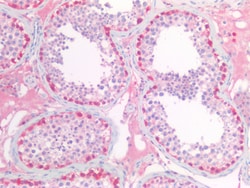

PGP9.5 (Protein gene product 9.5, UCH-L1, PARK5) is a neuron specific protein, structurally and immunologically distinct from neuron specific enolase. PGP9.5 has a molecular weight of 27 kDa and was first identified by high resolution two dimensional PAGE. PGP9.5 is a member of ubiquitin carboxyl-terminal hydrolase family 1 (peptidase family C12) with a ubiquitin carboxyl-terminal hydrolase domain. PGP9.5 is well known for having ubiquitin hydrolase and ligase activities that hydrolyzes small C-terminal adducts of ubiquitin to generate ubiquitin monomers. PGP9.5 is present in neurons and nerve fibers at all levels of the central and peripheral nervous system, in neuroendocrine cells, in segments of the renal tubules, in spermatogonia and Leydig cells of the testis, in ova and in some cells of both the pregnant and non-pregnant corpus luteum. Over expression of PGP9.5 leads to non-small cell lung cancer while decreased expression leads to Huntington disease and Alzheimer disease. Since PGP9.5 is present in cellular inclusions, it can be a useful as a neuronal marker and in the studies of neurodegenerative disorders such as with Parkinson disease.

| Immunohistochemistry (Paraffin), Western Blot, Western Blot | |